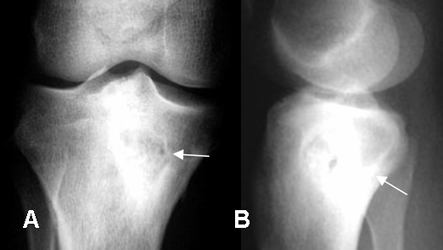

Fig 40. Osteomielitis crónica.

A: Rx AP y B: Rx lateral. Aumento en la densidad de la región epifisometafisiaria de la tibia, como secuelas de osteomielitis curada.

Fig 41. Osteomielitis crónica.

A: Rx AP y B: Rx lateral. Aumento de la densidad y engrosamiento de la diáfisis femoral, como secuela de osteomielitis tratada.